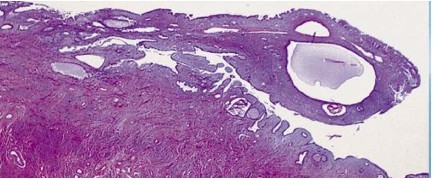

The following sample was taken from the cervix of a 35 year old woman. What is the diagnosis and treatment?

Cervical in situ neoplasia: Squamous neoplasia arizing at the squamocolumnar junction (transformation zone)

Invasiveness peaks between age 40 and 60, while in-situ (CIN) is in patients under 40

The most common cause is HPV infection (16 and 18), correlating with multiple partners and early age of coitus, cigarette smoking. HPV in 70% invasive squamous carcinomas

Low grade CIN= episomal virus replicates and accumulates in cytoplasm–> koilocyte; causes cell death

High grade CIN (below)= virus integrates into genome–> viral protein production–> inactivation of tumor suppressor genes (p53 and pRb) * takes ~ 10 years to progress from low to high grade

Treatment: culposcopy/removal of lesion tissue to prevent progression

Prognosis: 90% survival in developed nations